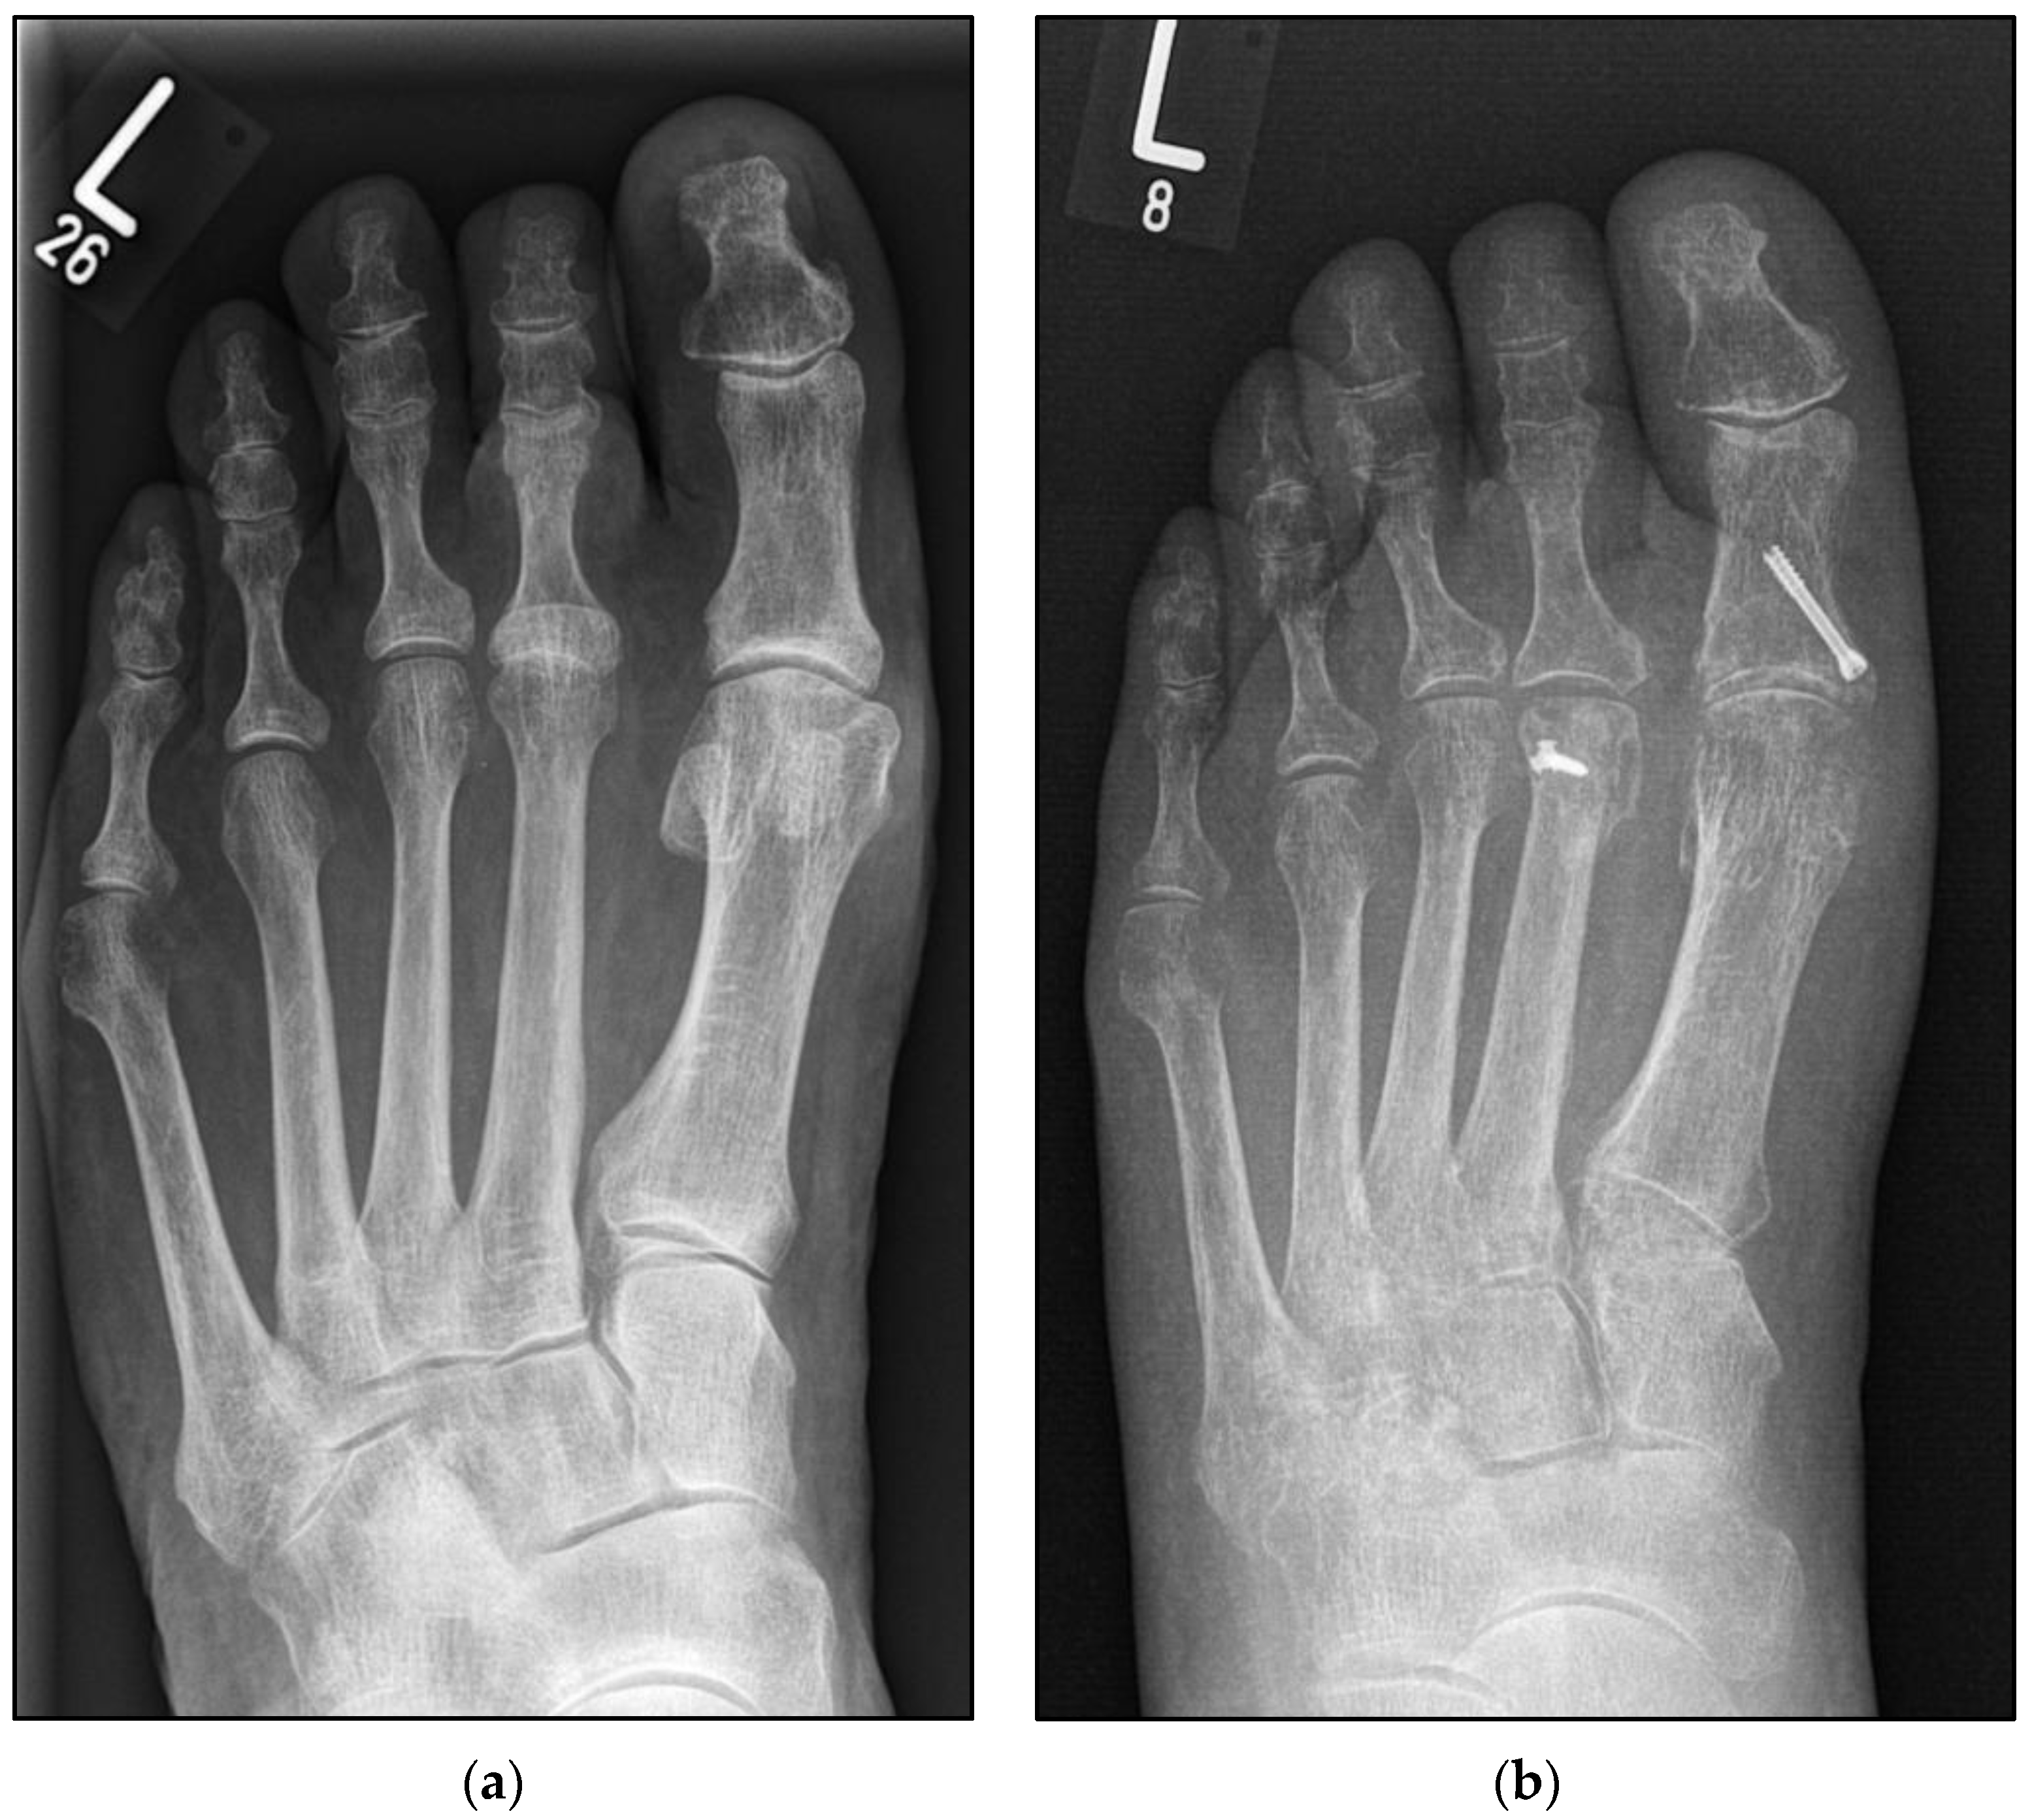

The Conventional Weil Osteotomy Does Not Require Screw Fixation

2.3. Surgical Procedure Using the Second Metatarsal as an Example